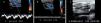

A través del modo B se puede ver directamente la presencia de un trombo o una vena no colapsable a la presión lo que indica que su lumen está ocupado (fig 8a).

Con los tres métodos de doppler, bajando al máximo el PRF y los filtros, se demuestra la falta de flujo en el vaso (Fig 8b).

Mientras más reciente es el trombo se observa más hipoecogénico con el lumen del vaso aumentado. La trombosis antigua se ve como un trombo ecogénico, retraído y con un vaso de menor calibre (fig 8).